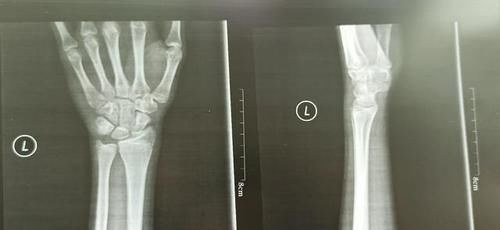

现在我家孩子15岁半了,身高只有167cm,体重49公斤。感觉好几个月都没怎么长高。去医院拍了骨龄照,结果不是很理想。

文章插图

这种情况应该没有什么长高的空间了。有点后悔当初自行停药,应该给孩子再接着打生长激素的。但是没有后悔药吃。

预约了下周的医生,看看能否再接着进行药物干预。